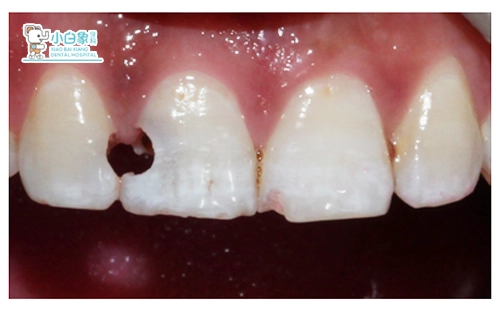

检查:颌面部未见异常。舌侧见烟渍沉着。11远中龋坏达牙本质深层,远中边缘达龈下0.5mm,叩(土),温度测试敏感;12近中龋坏达牙本质深层,叩(—),温度测试正常,牙龈无红肿。21近中缺损达釉质层,温度测试正常。

X线检查:11远中低密度暗影达髓腔,12近中低密度暗影近髓,根尖未见明显异常。

诊断:色素沉着;11牙髓炎;12深龋;21牙体缺损。